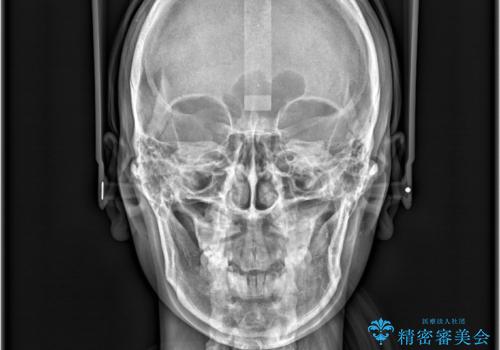

- 歯のデコボコ(叢生)を主訴にご来院された患者様です。

精密矯正検査を行った結果、歯を抜かずに行う、非抜歯のワイヤー矯正で治療を行う方針となりました。

歯並びの乱れに加え、**反対咬合(上下のかみ合わせのズレ)**も認められたため、見た目だけでなく、かみ合わせの改善も同時に行っています。